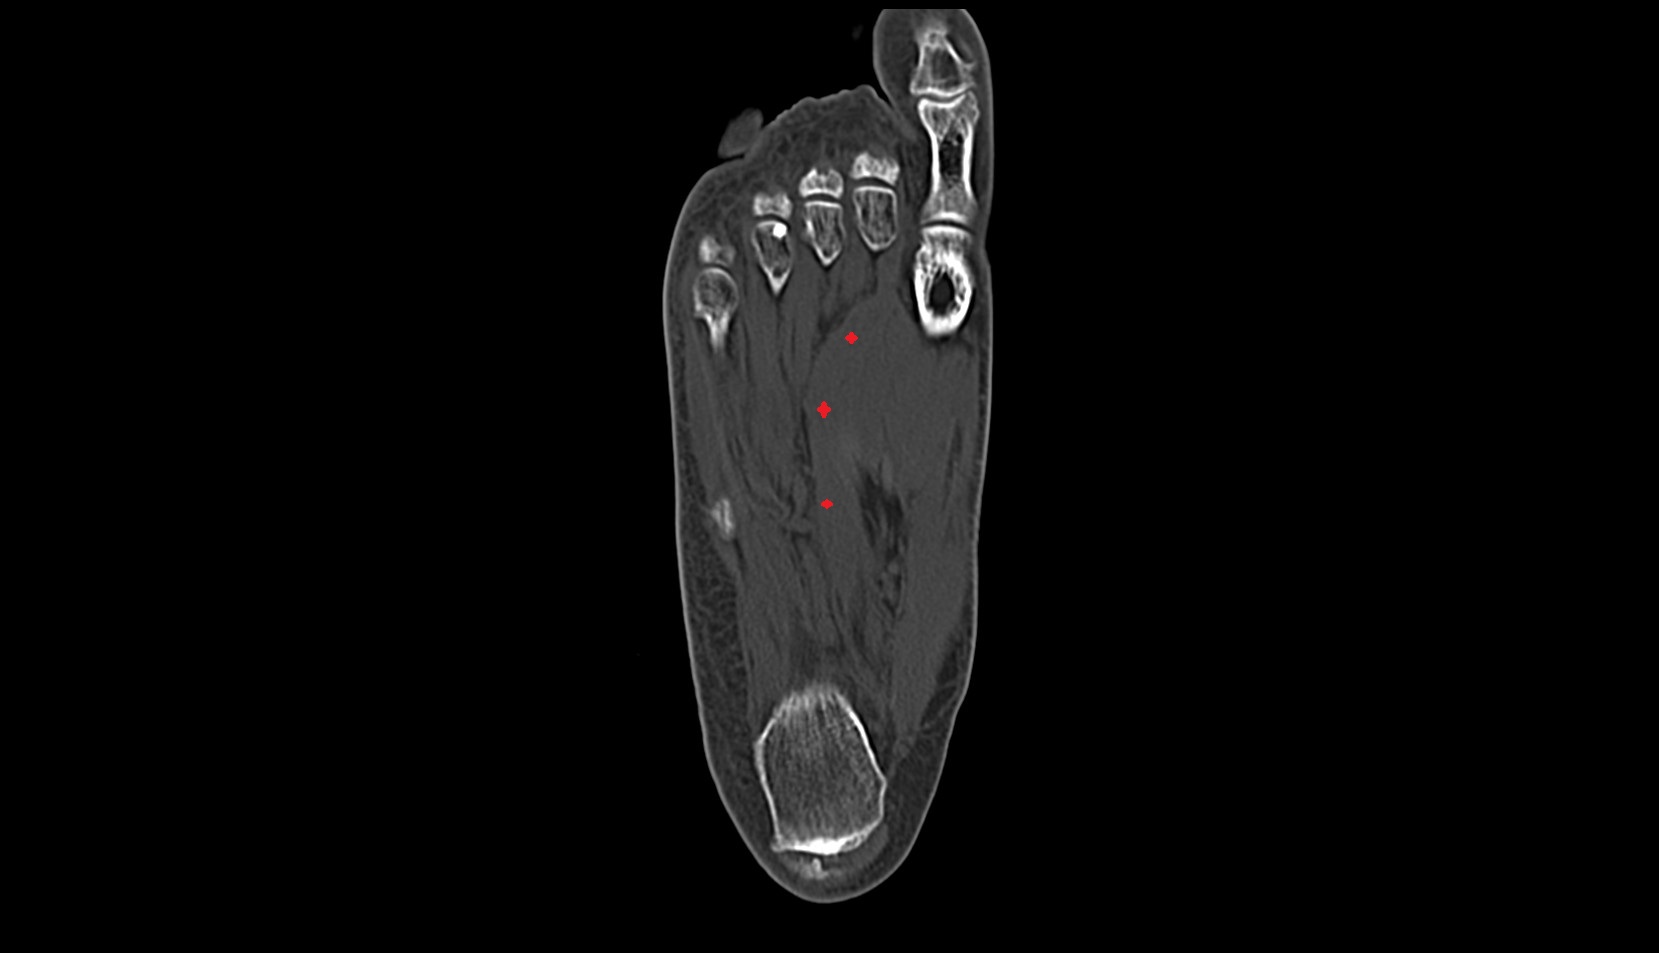

- Plantar aponeurosis